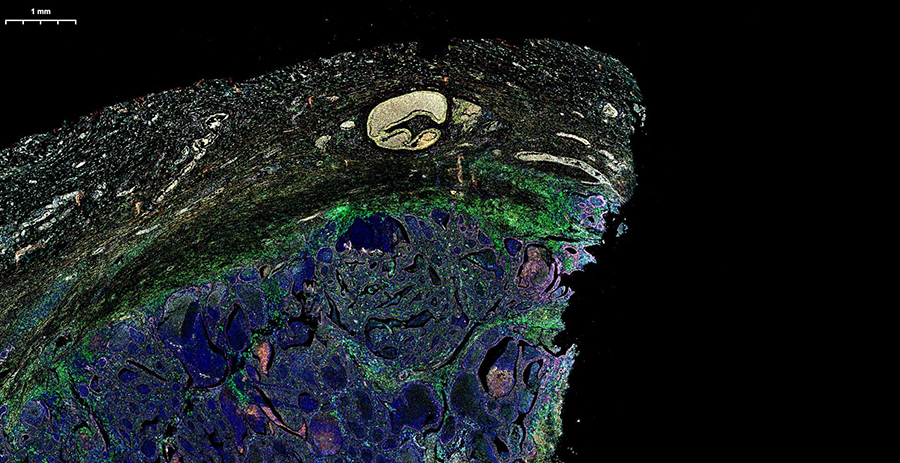

Погрузитесь в будущее гистологической лаборатории на двухдневном мероприятии, где представится возможность поработать с новейшим гистосканером LG-S80 от Servicebio.Погрузитесь в будущее гистологической лаборатории на двухдневном мероприятии, где представится возможность поработать с новейшим гистосканером LG-S80 от Servicebio.

Сможете оценить высочайшее разрешение, скорость обработки (полное стекло за 3-5 минут) и интеллектуальное аналитическое ПО, которое автоматически распознаёт структуры и формирует количественные отчёты с готовыми данными. Можно принести для апробации свои образцы, демонстрируемая конфигурация флуоресцентных каналов (Ex/Em, нм):